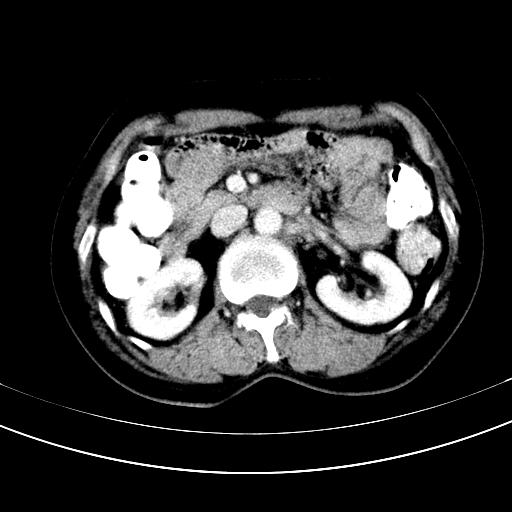

标题: CT12767:肝脏病变请会诊

补充强化片

胃内见充盈缺损,建议行胃镜病理检查,如果胃内无占位,则肝内考虑左叶、尾叶为包膜型肝癌,如有则考虑为转移瘤

胃内见充盈缺损,建议行胃镜病理检查,如果胃内无占位,则肝内考虑左叶、尾叶为包膜型肝癌,如有则考虑为转移瘤,左侧肾上腺 明显增大,成结节改变,本人考虑转移瘤可能性大。

胃内的充盈缺损因胃壁不厚,我个人考虑为胃内残留物。肝左叶及尾叶病灶,我首先考虑血管瘤,其次为肝癌。(尾叶的更低密度区太规整)

肝脏左叶和尾叶均见略低密度影,尾叶病变内见坏死?其边界清晰,形态规整1血管瘤,2肝癌待排

胆囊内见一略高密度影,息肉?

1.肝左叶及尾叶占位建议增强2.肝硬化

肝脏左叶和尾叶均见略低密度影,尾叶病变内见坏死?其边界清晰,形态规整1血管瘤,2肝癌待排3建议增强。

胃内充盈缺损考虑为胃内存留物,肝左叶和尾状叶两个病灶,均为低密度,建议增强。

考虑:胃体小弯侧胃癌(或平滑肌瘤恶化或平滑肌肉瘤)伴肝转移,左侧肾上腺转移不除外.

胃内充盈缺损考虑为肿瘤,肝尾叶及左叶肿块考虑转移瘤

胃癌肝内转移及肾上腺转移。

胃窦部占位伴肝及左肾上腺转移可能大,建议增强扫描。

肝脏左叶和尾叶均见略低密度影,尾叶病变内见坏死?其边界清晰,形态规整1血管瘤,2肝癌待排3建议增强或结合临床及超声与实验室检查

肝左叶及尾叶低密度灶,增强有渐进性明显强化,考虑血管瘤。胃内“充缺”首先要排除异物(食物),变换体位可鉴别。增强时机抓的不好,还应该有延时像。

谢谢楼主的增强片子,平扫没发现左侧肾上腺的问题很不好意思,可惜片子只有门脉期,所以还只有猜,肝脏的病灶在门脉期部分强化,首先考虑为血管瘤(其他的用一种病不好解释)胃要喝水就好了现在不好说是否有问题,左肾上腺的问题考虑是肿瘤。

做了增强后,可以明确胃是没有肿瘤的,肾上腺也没有肿瘤.肝左叶的病灶首先考虑血管瘤,应该再延迟,肝尾状叶的病灶仍不能排除肝癌的可能性.